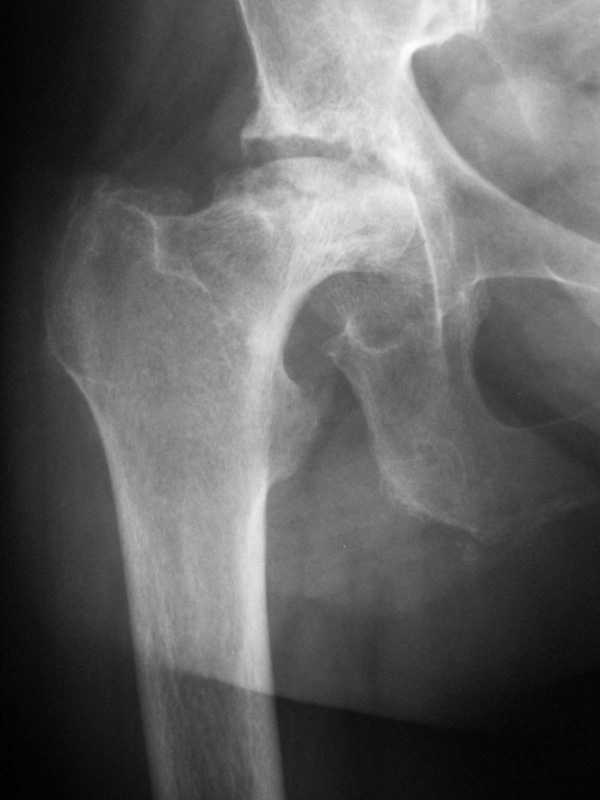

Фото с головкой не получил. Но скорее всего у больного алкаптонурия, а черное окрашивание тканей - это одно из ее проявлений - т.н. охроноз. У

нас было подобное наблюдение (см. фото).

Несколько лет назад оперировали женщину по поводу правостороннего коксартроза с выраженной кистозной перестройкой и импрессией головки - аналогичные макроскопические изменения - абсолютно черная деформированная головка и черная импрегнация внутренней поверхности капсулы. Испугались, протез не поставили.Гистологическое заключение - предварительное - меланома?, окончательное -импрегнация гемосидерином. Установили протез - без осложненийПо клинике и динамике на рентгенограммах имел место перелом стенки костной кисты и геартроз с исходом в "гемосидероз". В октябре прошлого года оперировали ту же больную на втором т\б суставе. Картина аналогичная. Во второй раз не испугались - исхотд благополучный